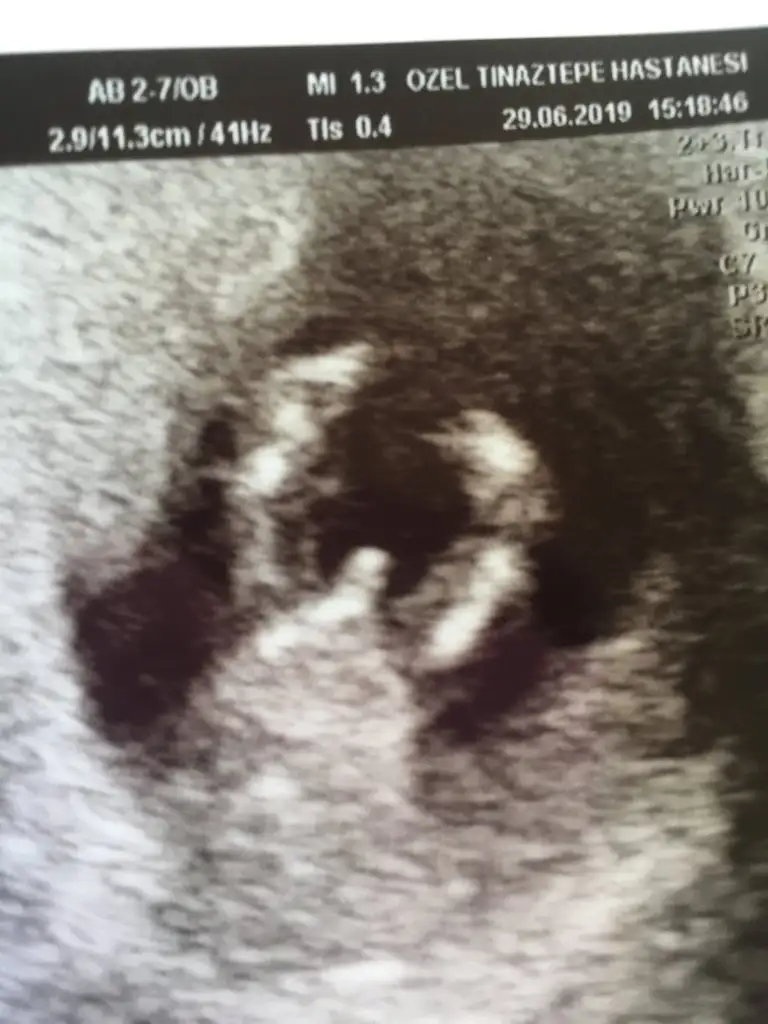

Lekelenmen için ne dedi dr cnmHerkese merhaba benim sat 11 nisan a göre 12+0 haftalık hamileyim yarın ikili testim var cinsiyet konusunda hiç bir tahmin vs yok hafif lekelenmem vardı doktor ona baktı ikili test içinde yarına sıra verdi buda benim minnoşum dünkü fotoğrafı çokta net değil ama olsunEki Görüntüle 2285205

Evet canım baktıkça öğreniyo insanBende sanırım nub tan anlamaya başladımokadar arastırdımki bende erkek demıstım hemde resmen erkek yazmıstım sende öyle yazınca dedim sanırım ben bu işi ögrendim

Tam net belli değil maalesef hareketli poz almış dr galiba ben emin olamadım %50 %50bir oglum var şükür. bu da kiz olsa iyi olur ama erkek olursa da baş taciyaa merkez mi ilcesi mi ?